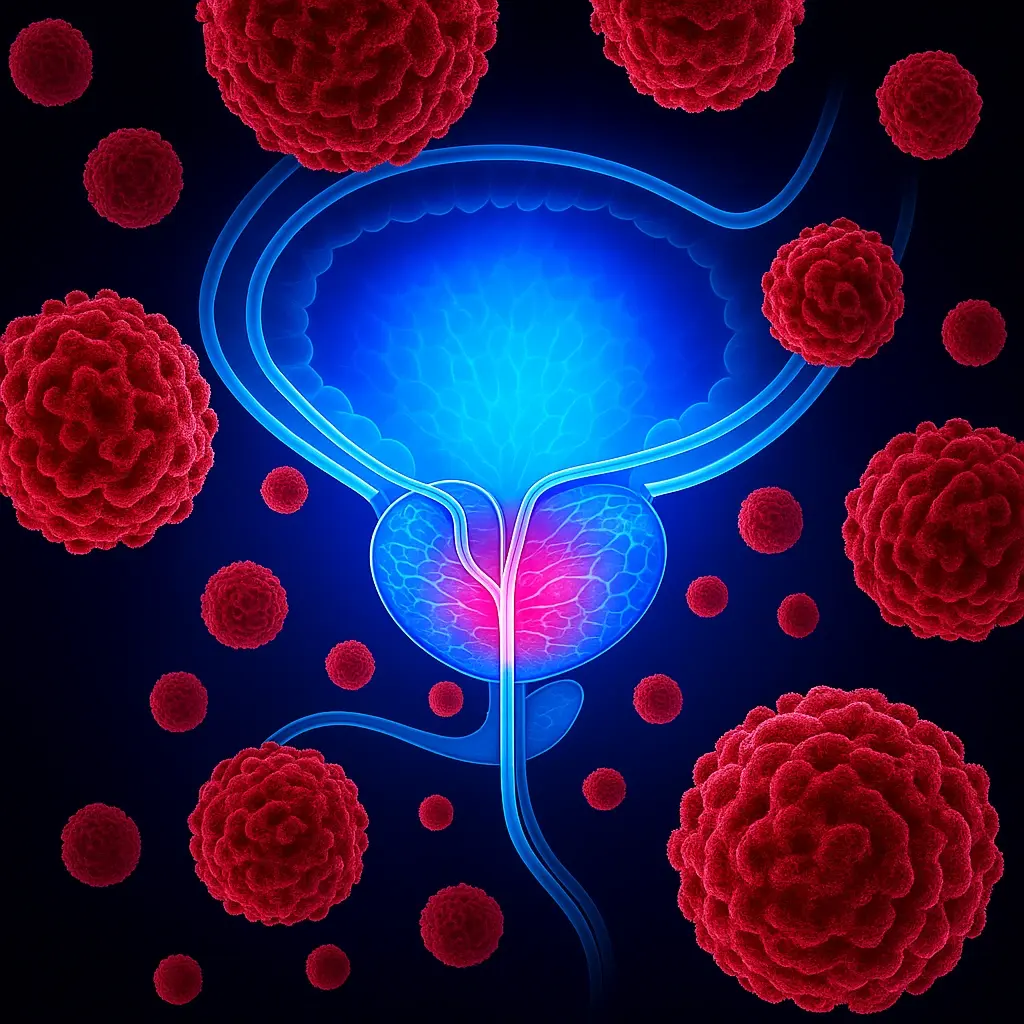

Waking Up 3–6 Times a Night Just to Pee and Still Feeling Your Bladder Is Full? This Condition Could Be Draining More Than Just Your Sleep…

Researchers at Johns Hopkins point to a rarely mentioned factor linked to enlarged prostate that may explain why nighttime urination keeps getting worse with time.

Researchers at Johns Hopkins point to a rarely mentioned factor linked to enlarged prostate that may explain why nighttime urination keeps getting worse with time. They also reveal a surprisingly simple 12 second method most men never hear about until sleep, confidence, and quality of life are already compromised.

THE REAL DANGER ISN’T WHAT YOU FEEL — IT’S WHAT YOU CAN’T SEE. There is a hidden biological agent — a silent bacteria that quietly irritates the prostate — silently settling inside the prostate and disrupting the gland’s natural rhythm night after night. And no one ever told you! It doesn’t behave like normal inflammation. It doesn’t go away on its own. And it doesn’t stop until the constant pressure on the prostate — and a man’s vitality — becomes impossible to ignore. That’s why the stream weakens… why the bladder never feels empty… why nights keep getting worse… even when you do everything right. That’s why men just like you are watching this right now. If I were you, I wouldn’t ignore this.